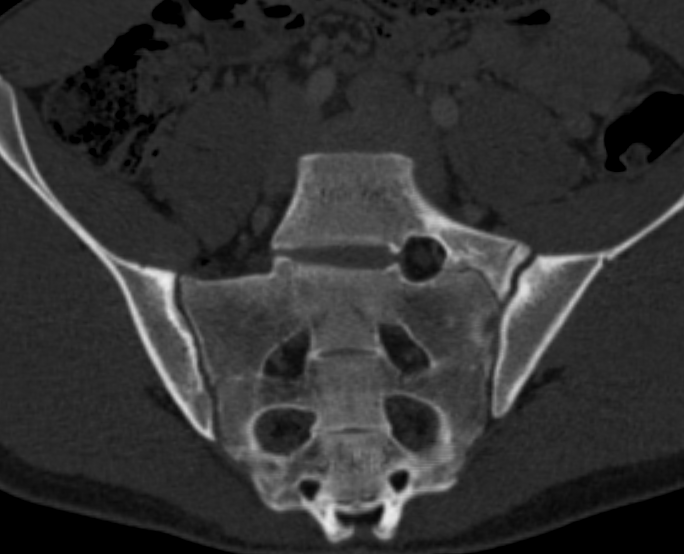

3. Bertolotti Syndrome